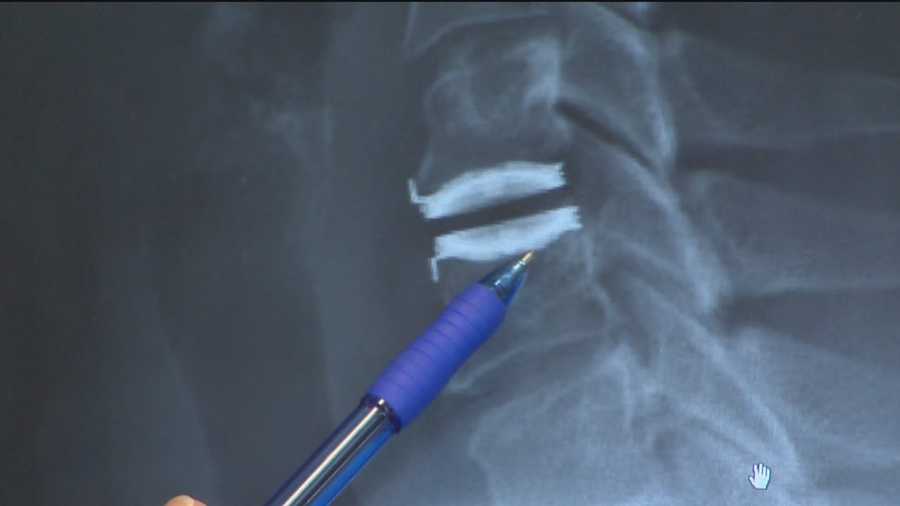

From www.wbaltv.com

Surgery helps fix disc, nerve problems in neck Neck Disc Tingling An irritated nerve root can cause pain, numbness, tingling and even cause you to lose some of the strength of your arm. Cervical radiculopathy (also known as “ pinched nerve ”) is a condition that results in neurological dysfunction caused by compression and. The most common levels of disc herniation are c4/5, c5/6 and c6/7. These types of symptoms can. Neck Disc Tingling.